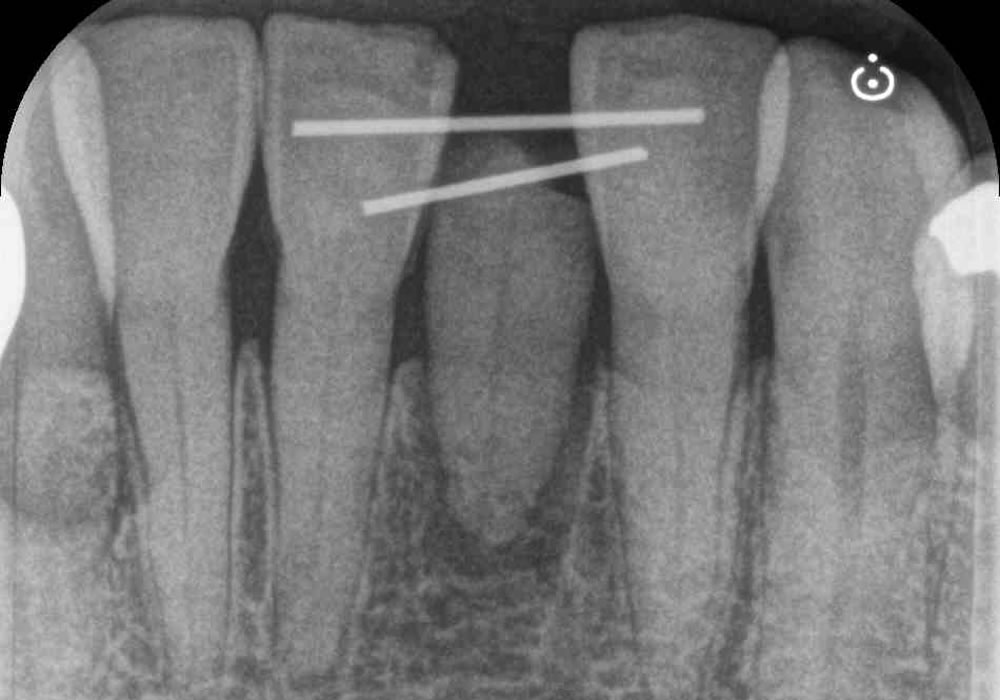

下の前歯が根元から折れてしまった患者さんのレントゲン写真です。黄色丸枠のところが折れてしまった箇所になります。

局所のレントゲン写真により、歯の上の部分は確かに折れてなくなっていますが、根の部分はしっかりと残っていることがわかります。

しかし、根を保存するにしてもフェルール効果を得るためには根の位置を変える必要があります。

術直後のレントゲン写真です。術前のレントゲンを比べると歯の位置が上になっているのがわかります。

術後2週目から根管治療を行い、根管充填を行った後のレントゲン写真です。

根を引き上げた部分が白くなっており、しっかりと骨が出来ているのがわかります。